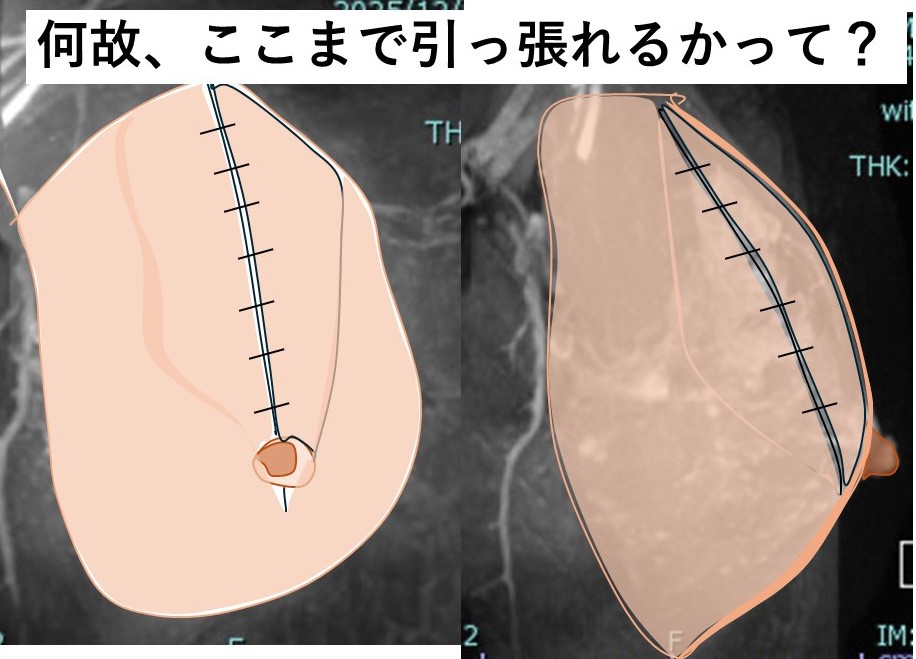

7. 乳腺の縫合閉鎖

結構大きい欠損なのに、乳腺がそんなに(縫合できるほど)伸びるのか??

8. それには訳があります。

乳腺は「厚み」があるので、それを「薄く引き伸ばす」イメージです。